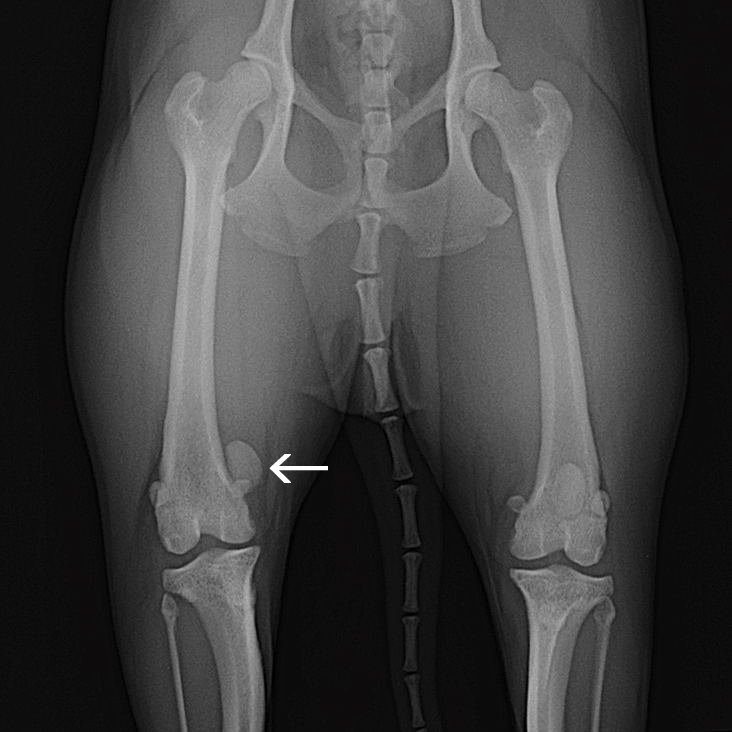

矢印 内側にずれている膝蓋骨   正常な位置にある膝蓋骨